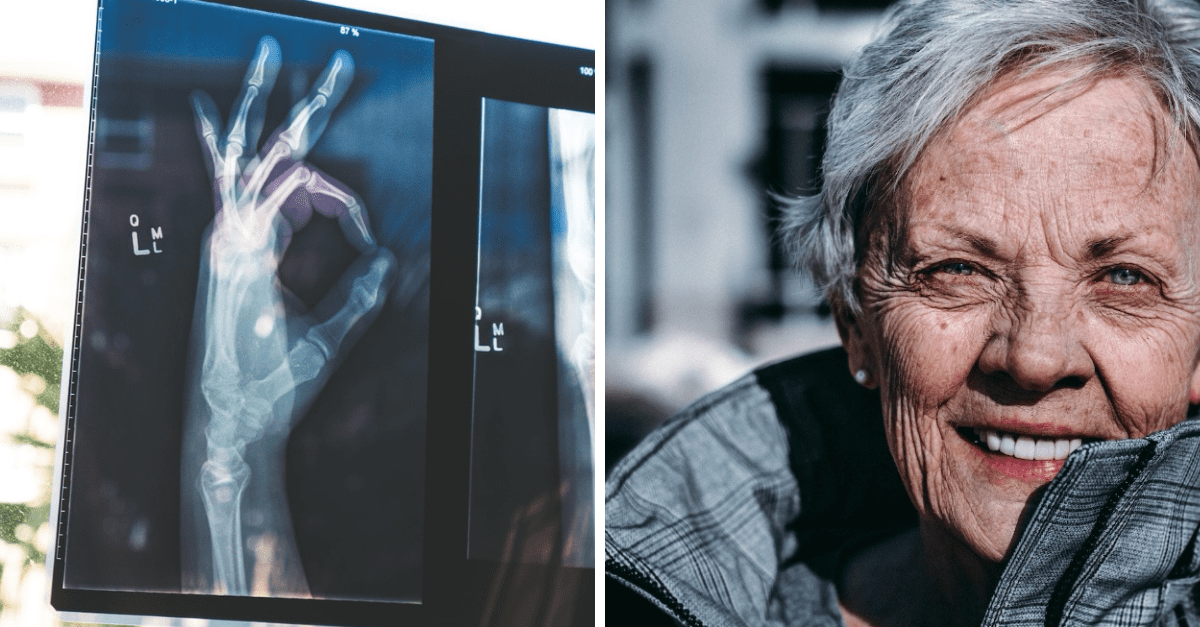

Vaše kosti krehnú

Tak ako sa dokáže regenerovať koža, aj kosť za života podlieha regenerácii za účasti buniek osteoklastov a osteoblastov, zjednodušene povedané, sa kosť odbúrava a následne prebieha znovu výstavba.

Pri starnutí sa však telo prestáva regenerovať tak rýchlo ako v mladosti, čo znamená, že sa môže vyvinúť osteoporóza, ktorá napríklad u žien súvisí aj s poklesom estrogénu počas menopauzy, alebo u mužov s poklesom testosterónu. Prispieva k tomu i fajčenie a častá konzumácia alkoholu. Kosti sa stávajú slabé, krehké, čo vedie k poruche držania tela, bolesti a väčšiemu riziku zlomenín.